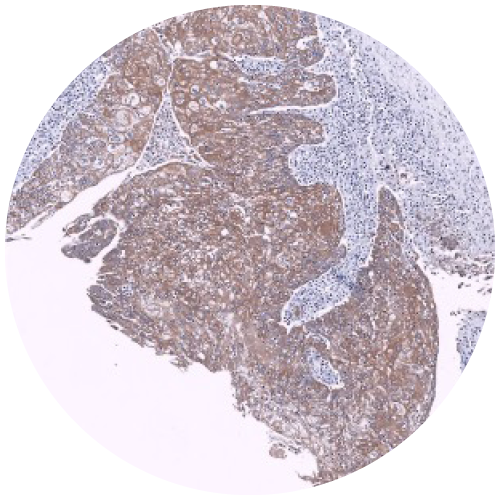

Physical IHC

ViewsML uses deep learning to eliminate physical staining, delivering virtual results in seconds at a fraction of the cost, all the while fitting into existing workflows.

Virtual IHC